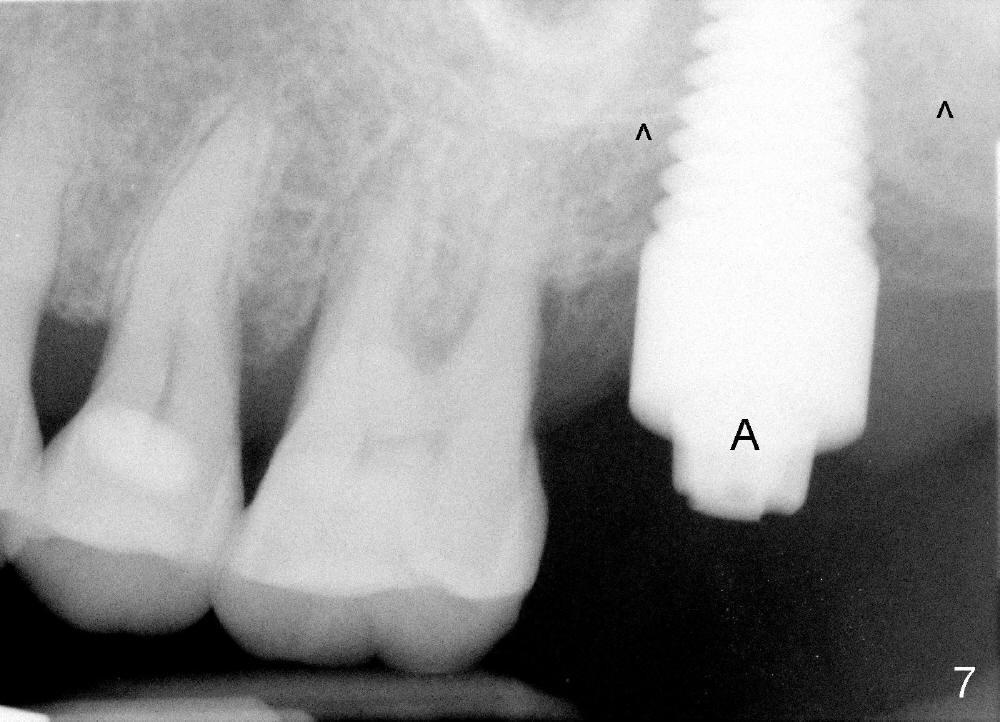

Next time she returns 4.5 months postop, bone looks normal around the implant (Fig.7), whereas the buccal gingival recession appears to get worse with 1-2 implant thread exposure (Fig.8 >). To avoid this complication, the initial osteotomy should be placed as palatal as possible; when the implant is placed with gingival recession (Fig.5), soft tissue graft should be performed. The implant should be smaller.